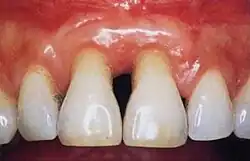

Gingivitis is a common condition that affects the gingiva or mucosal tissues that surround the teeth. The condition is a form of periodontal disease; however, it is the least devastating, in that it does not involve irreversible damage or changes to the periodontium (gingiva, periodontal ligament, cementum or alveolar bone). It is commonly detected by patients when gingival bleeding occurs spontaneously during brushing or eating. It is also characterized by generalized inflammation, swelling, and redness of the mucosal tissues. Gingivitis is typically painless and is most commonly a result of plaque biofilm accumulation, in association with reduced or poor oral hygiene. Other factors may increase a person's risk of gingivitis, including but not limited to systemic conditions such as uncontrolled diabetes mellitus and some medications. The signs and symptoms of gingivitis can be reversed through improved oral hygiene measures and increased plaque disruption. If left untreated, gingivitis has the potential to progress to periodontitis and other related diseases that are more detrimental to periodontal and general health.[10]

Healthy gingiva can be described as stippled, pale or coral pink in Caucasian people, with various degrees of pigmentation in other races.[15] The gingival margin is located at the cemento-enamel junction without the presence of pathology. The gingival pocket between the tooth and the gingival should be no deeper than 1–3mm to be considered healthy. There is also the absence of bleeding on gentle probing.[11]